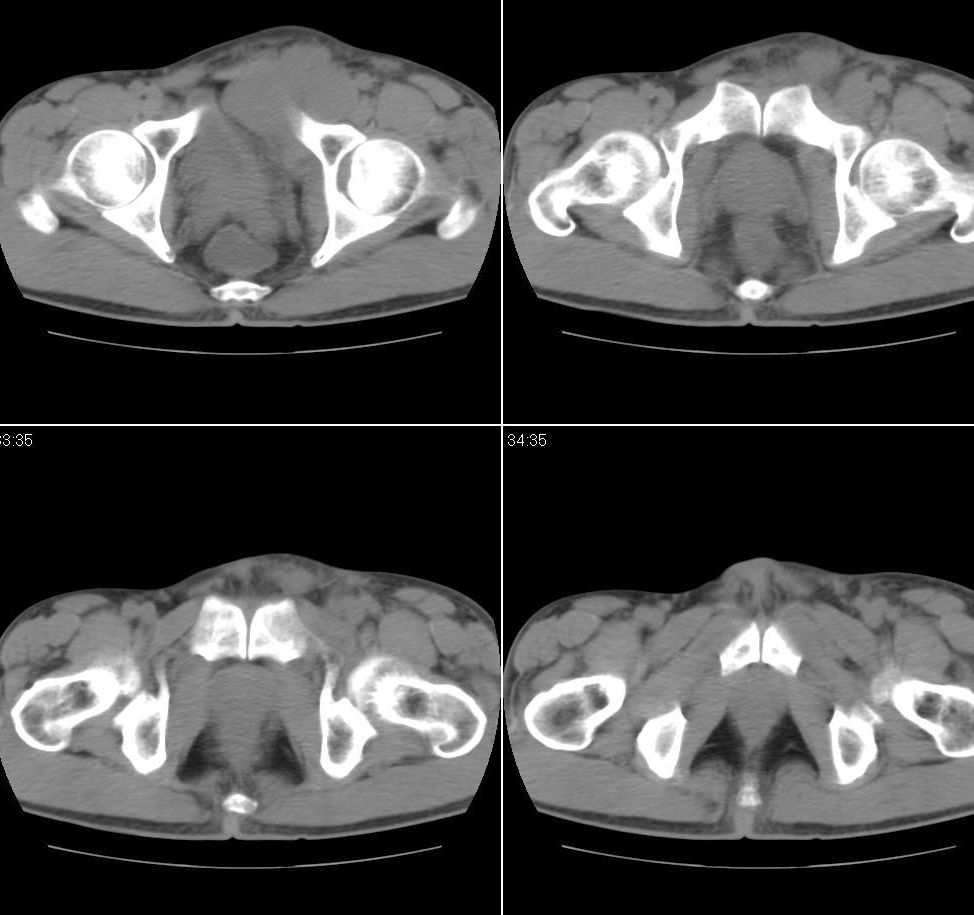

以下是引用jiangjing在2007-9-18 17:20:00的发言:[br]考虑生殖细胞肿瘤伴腹腔及腹膜后与腹股沟区淋巴转移,腹膜后大血管受压受侵

以下是引用老爱克斯新网客在2007-9-18 18:27:00的发言:[br]主动脉旁左侧腹股沟可见多发结节状病灶,1淋巴瘤,2转移瘤待除外,